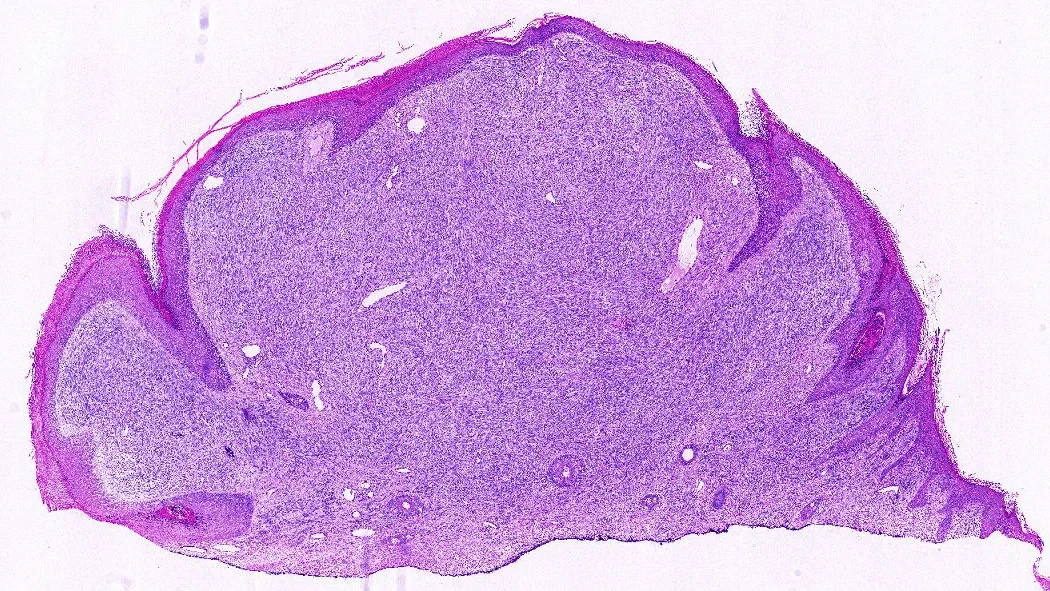

A hematoxylin and eosin (H&E) slide of a sarcoma, specifically a rhabdomyosarcoma.

When people think of AI, they often imagine large language models that generate text. Thiesen’s system is different: it analyzes images—specifically, digitized pathology slides stained with hematoxylin and eosin (H&E). Pathologists examine these slides for subtle patterns in cell shape, clustering, and texture. The AI can scan for the same things, at scale, breaking each slide into thousands of tiles, converting them into numerical “fingerprints,” and assembling a prediction of which sarcoma subtype the tumor most resembles.